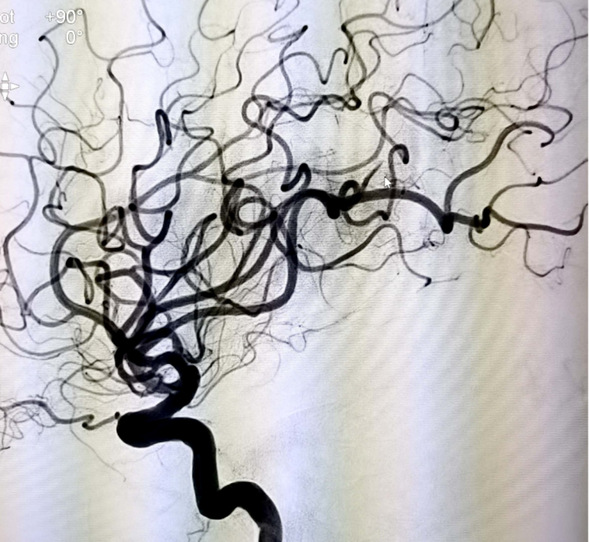

术后颈内动脉正位造影

术后颈内动脉侧位造影